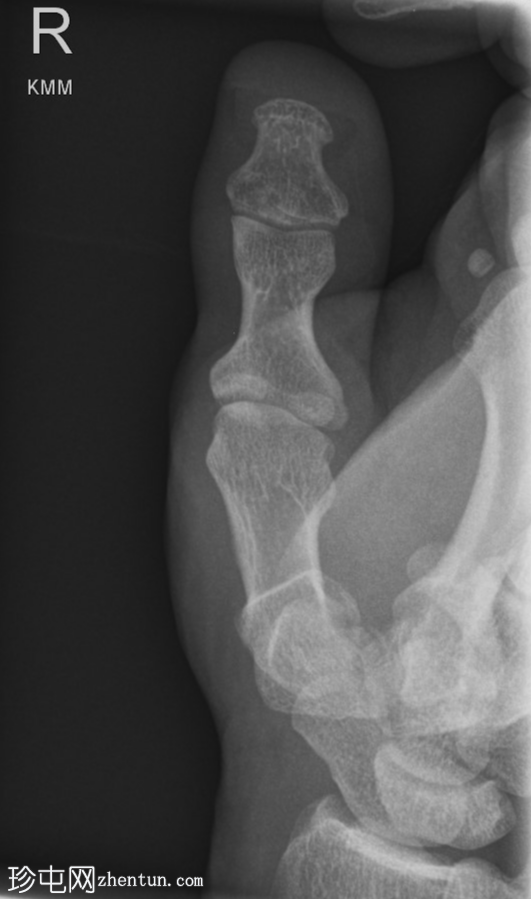

侧位

右拇指远节指骨掌侧关节内轻度移位骨折,可能为撕脱性骨折。关节内可见轻微皮质台阶。

第一掌骨基底部可见轻微移位骨折,根据骨折轨迹推测可能为关节内骨折,但关节内皮质台阶不明显。若临床治疗方案改变,可能需要进一步

影像

学检查。第一腕掌关节解剖对位良好。